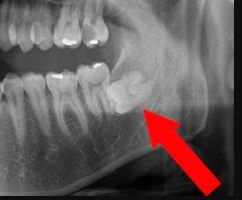

横向き親知らずの抜歯

です!

こういう状況ですw

親知らずが、あろうことか真横に生えてきていて、

奥歯(大臼歯)にめり込んでいるんです

このままいくと、大臼歯が死滅してしまうので、親知らずを抜いておきましょう!

ということになったんです。